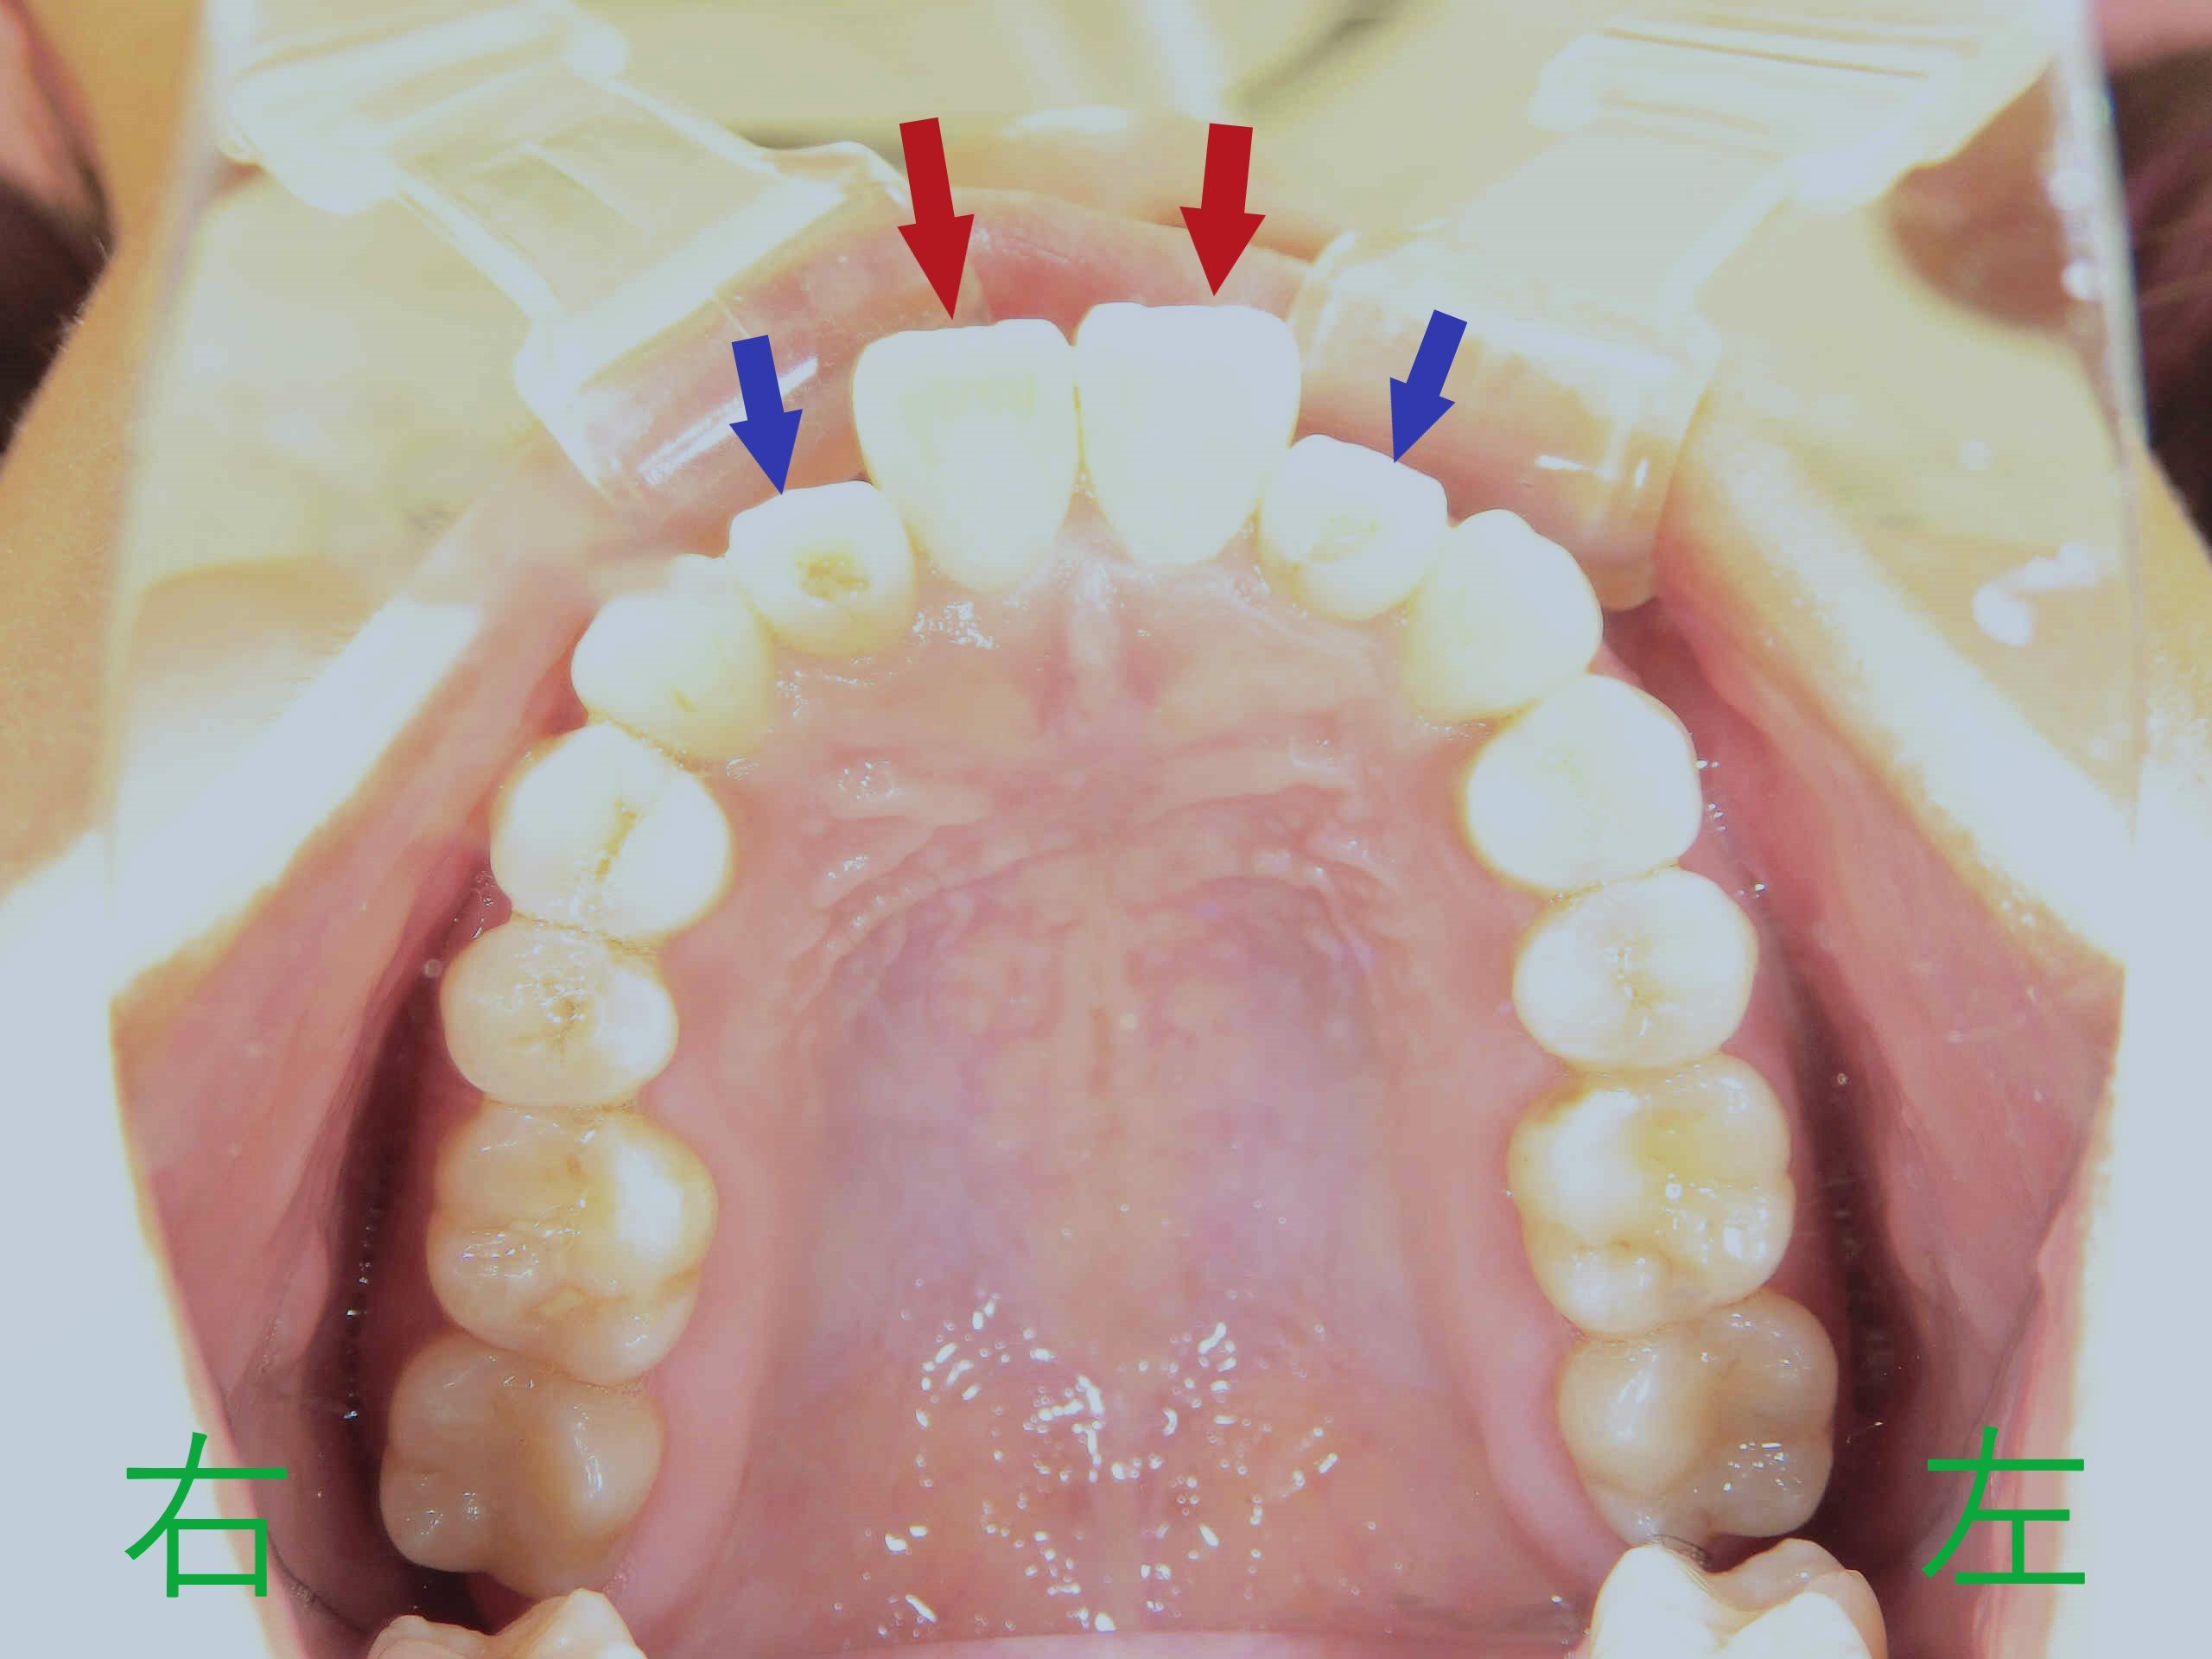

患者本人は、以前より上顎左右中切歯(赤色矢印)の前突感(いわゆる出っ歯)と、上顎左右側切歯(青色矢印)の逆被蓋(下顎前歯より内側に位置している状態)を気にされていました。

写真は前歯の噛み合わせを下から見上げたもので、上顎左右中切歯が前方に出ており、左右側切歯が内側に位置していることが確認できます。

左の写真は、矯正治療開始から3か月後の上顎の様子です。上顎左右中切歯の前突感が緩和され、左右側切歯が内側から外側へと移動しつつあることが確認できます。

右の写真は上下の噛み合わせを下から見上げたもので、下顎前歯が内側に移動し、それに伴い上顎中切歯も内側に移動。前突感の軽減が明瞭です。側切歯の外側移動も進行中ですが、改善の余地が残ります。